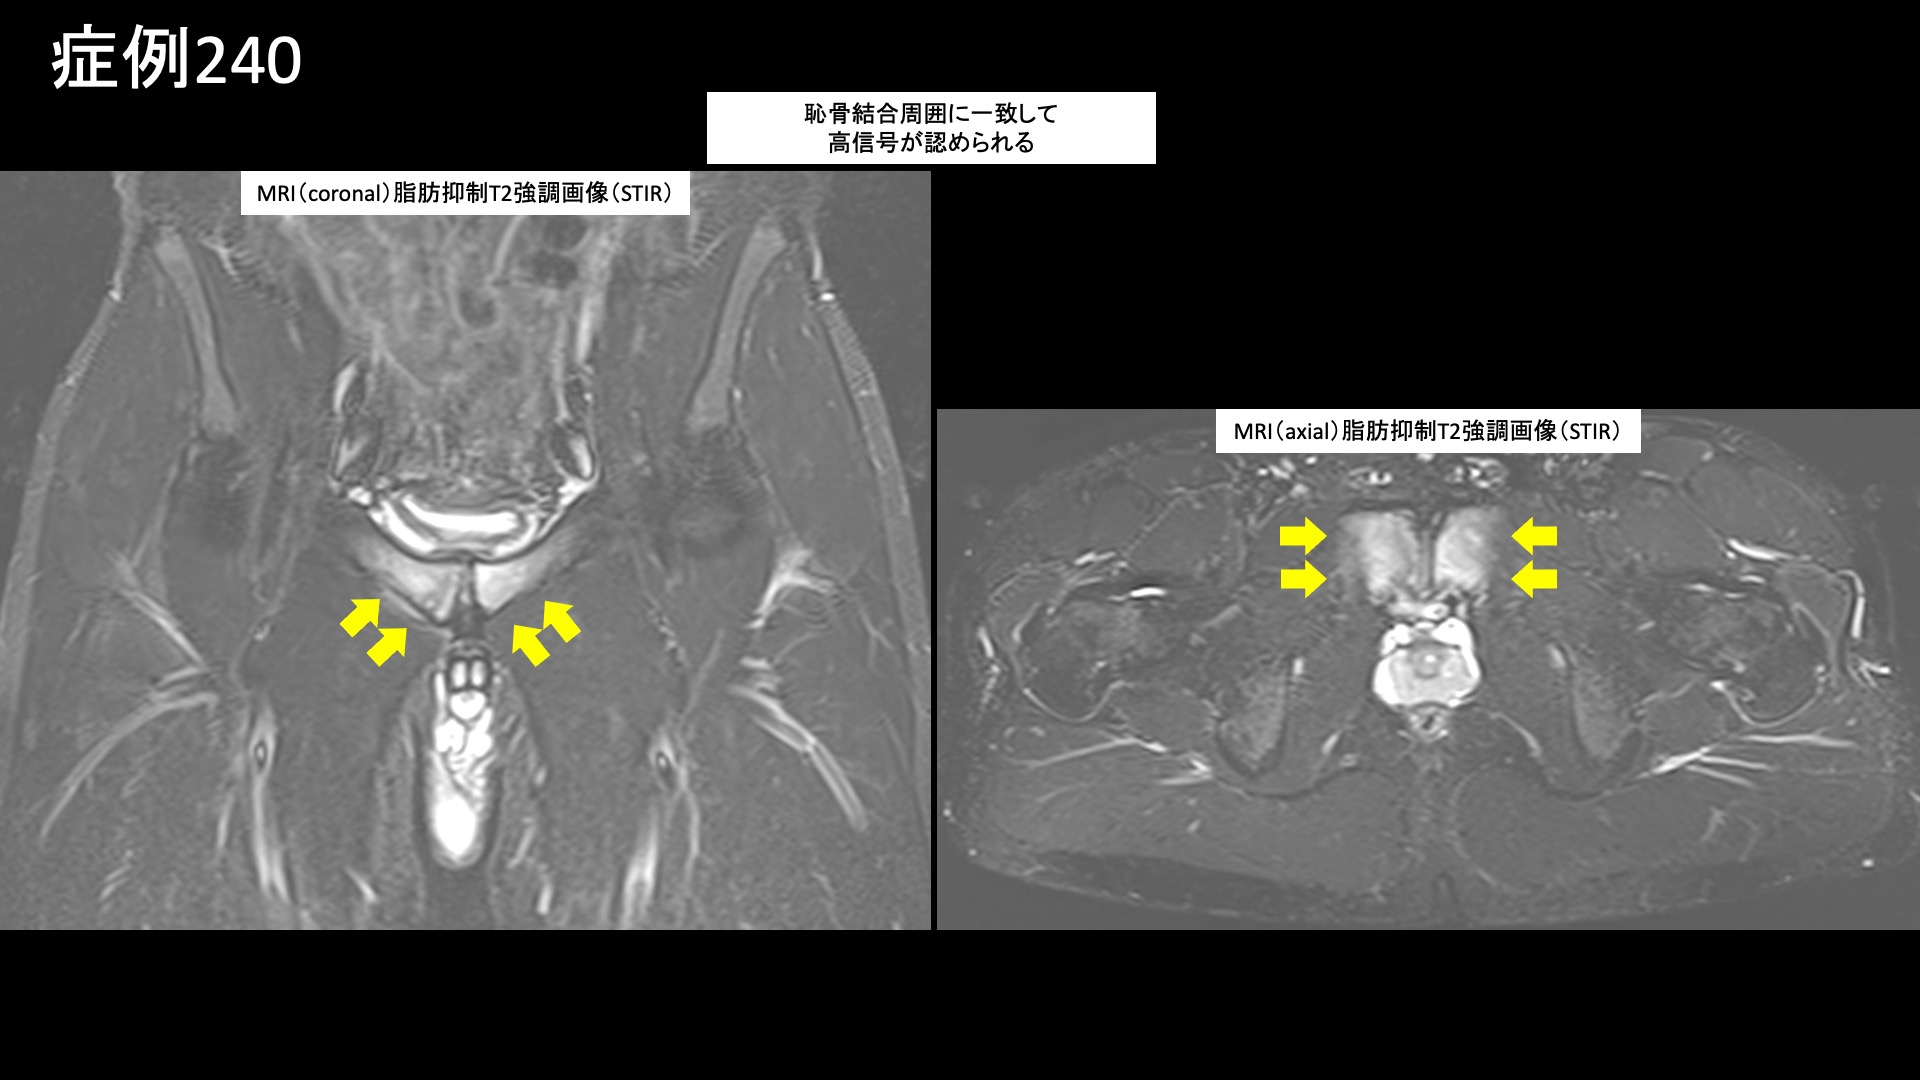

股:変形性股関節症など 【10代:男性】恥骨が痛くて走れない、スポーツが原因で生じた恥骨結合炎に対するモヤモヤ血管治療(恥骨結合炎) 2025.09.26 鴨井院長による動画解説 受診までの経過 スポーツが原因で、半年前から恥骨が痛むようになりました。日常生活では問題ないものの、ランニングで痛み走れなくなってしまいました。キック動作でも悪化しました。下腹部痛はなく、あくまでも恥骨に限局した痛みでした。MRI検査の結果、恥骨結合炎と診断されました。体外衝撃波治療や鍼治療を受けましたが改善しませんでした。十分安静療養をしてきたにもかかわらず、いつまでも治らないことから当院を受診されました。 診察時の所見 恥骨結合に一致して圧痛が見られましたが、少し広範囲に及んでいました。レントゲンでは恥骨結合が開大しており、結合面の骨表層は不整でした。MRI検査では、脂肪抑制T2強調画像において、恥骨結合周囲に高信号を明瞭に認めました。画像所見からは強い炎症が示唆され、日常生活で症状を生じても不思議ではない程度でした。治療適応と判断し、モヤモヤ血管(病的新生血管)に対する運動器カテーテル治療(微細動脈塞栓術)を受けていただきました。 治療の所見 血管造影を行うと、恥骨結合周囲に一致してモヤモヤ血管が濃染像として描出されました。治療後は画像上速やかに消失しました。その他複数個所の治療を行い終了しました。尚、治療時には恥骨結合における再現痛も確認できました。 *再現痛とは、薬液投与時に普段の痛みが一定程度再現される現象です。責任血管の同定のための参考とします。 治療後の経過 治療後2週間、激しい動作は控えていたため、まだ良くなっているかどうかはわかりませんでした。恥骨における圧痛は過敏さが無くなったものの、まだ比較的広範囲に認められました。治療後1ヶ月、走った後に少し違和感があるものの、ダッシュしてみても痛まなくなりました。患部を自分で押してみましたが痛くありませんでした。診察では、圧痛は強度・範囲とも大幅に減っていました。経過良好でした。その後、下半身の筋力トレーニングをした際に痛みが強くなることはあったものの、順調に経過し、治療後6ヶ月時点でもほとんど痛みなく過ごせているとのことでした。典型的な恥骨結合炎の症例でした。早期から改善し、再発なく経過されていて何よりでした。 【70代:男性】夜間痛がその日のうちに改善!強い炎症を伴った変形性膝関節症に対する運動器カテーテル治療(変形性膝関節症) 前の記事 【80代:男性】火が出るような痛みに襲われ夜も寝られず・・発症1ヶ月の頭部/顔面に生じた帯状疱疹後神経痛(帯状疱疹後神経痛) 次の記事